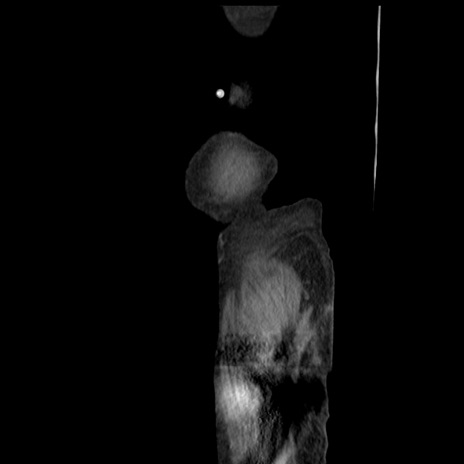

症例31(矢状断像)

【症例】80歳代 女性

【主訴】腹部膨満感

【現病歴】他院にて肝硬変にてフォロー中。1週間前から便秘、腹部膨満感、臍部腫瘤あり受診となる。

【既往歴】肝硬変

【身体所見】腹部膨隆あり、皮膚変化なし、疼痛なし。

【データ】WBC 4600、CRP 0.25